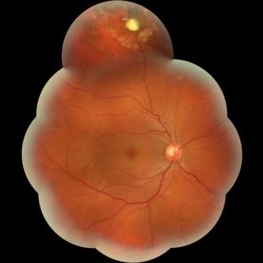

Best Disease Mar 9 2013 by Hamid Ahmadieh, MD Color fundus photograph the right eye of a 49-year-old man with decreased VA due to advanced Best disease. Photographer: Soodabeh Fooladin, Negah Eye Center, Tehran Condition/keywords: Best disease

Best Disease Mar 9 2013 by Hamid Ahmadieh, MD Color fundus photograph the left eye of a 49-year-old man with decreased VA due to advanced Best disease. Photographer: Soodabeh Fooladin, Negah Eye Center, Tehran Condition/keywords: Best disease